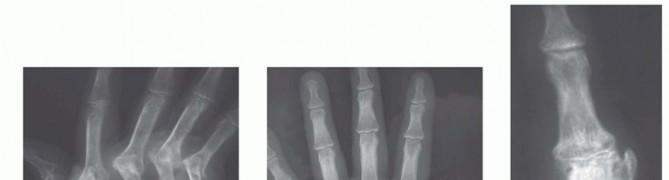

20 MIN READ Proximal Interphalangeal and Metacarpophalangeal Joint Silicone Implant Arthroplasty يناير 2023 Read More

23 MIN READ Proximal Interphalangeal and Metacarpophalangeal Joint Surface Replacement Arthroplasty يناير 2023 Read More